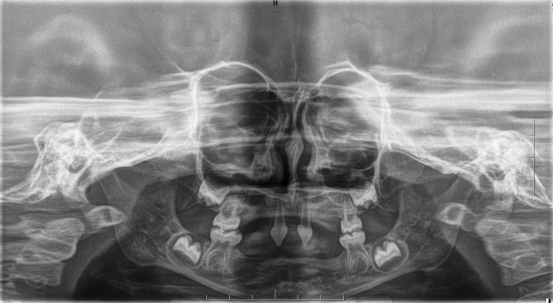

近年来,3044永利集团附属口腔医院(后文简称贵医口腔)在临床诊疗方面每年均有多个技术创新或突破。期间,副经理、口腔修复种植科主任医师王永曾带领团队完成多名外胚层发育不全患儿的可摘局部义齿及全口义齿修复,222日,更是为一位4岁患儿完成了罕见外胚层发育不全可摘局部义齿修复该患儿为目前口腔医院完成修复治疗年龄最小的患者

患者4岁,乳牙未正常萌出,上颌仅4下颌仅2颗乳牙,不能正常咀嚼,于2022年底在外地就诊多次无法修复,专程到口腔医院就诊。在后疫情时期,患者经王永门诊诊治后商讨出诊疗方案医院细心安排,于222由王永带领谭雯珈、姜炜鹏等医师,使用修复、正畸、修复工艺等多项技术,顺利完成了大面积乳牙缺失修复患儿现场进食效果良好,家长及患儿十分满意。

外胚层发育不全(ectodermal dysplasiaED),是一种先天性遗传病,发病率约为1/100000。临床主要表现为少汗或无汗,毛发稀疏,牙发育不全三联征。

因其口腔表征为先天缺牙甚至无牙颌,且缺牙患儿口内余留牙往往表现为锥形牙、釉质发育不良、牙槽嵴发育不良等,可严重影响患儿的咀嚼功能及面部软硬组织生长发育。